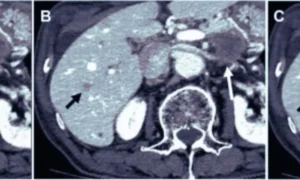

Pulsatile tinnitus, or a rhythmic noise heard within the ears, usually synchronized with the heartbeat, may be caused by vascular abnormalities of the brain, such as sigmoid sinus dehiscence. It is a condition whereby there is a loss of bony covering of the sigmoid sinus, leaving the vessel exposed and allowing sound to be conducted directly into the ear. It has come to be increasingly appreciated as a common venous etiology of tinnitus.

This cross-sectional study was carried out at Ain Shams University Hospitals between December 2023 and December 2024, a period of 12 months. The study recruited 36 patients who had pulsatile tinnitus and radiologically proven sigmoid sinus dehiscence. Tinnitus severity was clinically evaluated, and imaging grading of dehiscence was done. Blood samples were drawn to determine vitamin D levels, and statistical analysis of correlations between variables was done.